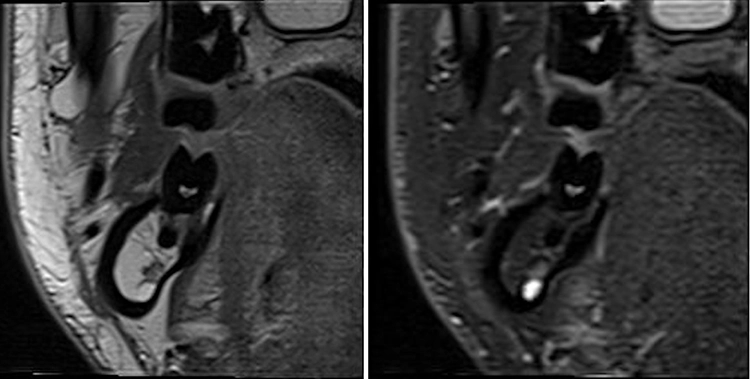

Im Jahr 2023 stellte Siemens in Kooperation mit Sirona ein Projekt für ein „dental dedicated MRT“ vor, bei dem ein speziell für die zahnmedizinischen Anforderungen maßgeschneidertes MRT entwickelt und auf den Markt gebracht werden soll.** Hier spielen die neuen technischen Möglichkeiten in der möglichen Größenreduktion und auch in reduzierten hardwareseitigen Anforderungen eine Rolle. Eine Arbeitsgruppe aus Aarhus betreibt bereits ein prototypisches Gerät [10]. Einige Aufnahmen dieses Prototyps sind in den Abbildungen 4 und 5 zu sehen. Das Gerät wurde auf der Konferenz der European Academy of Dentomaxillofacial Radiology (EADMFR) vom 12. bis 15. Juni 2024 offiziell vorgestellt.***